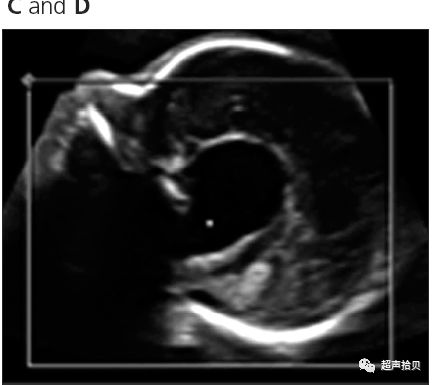

图1:横向声像图显示位于中线蛛网膜囊肿(C), 彩色多普勒没有血流显示;